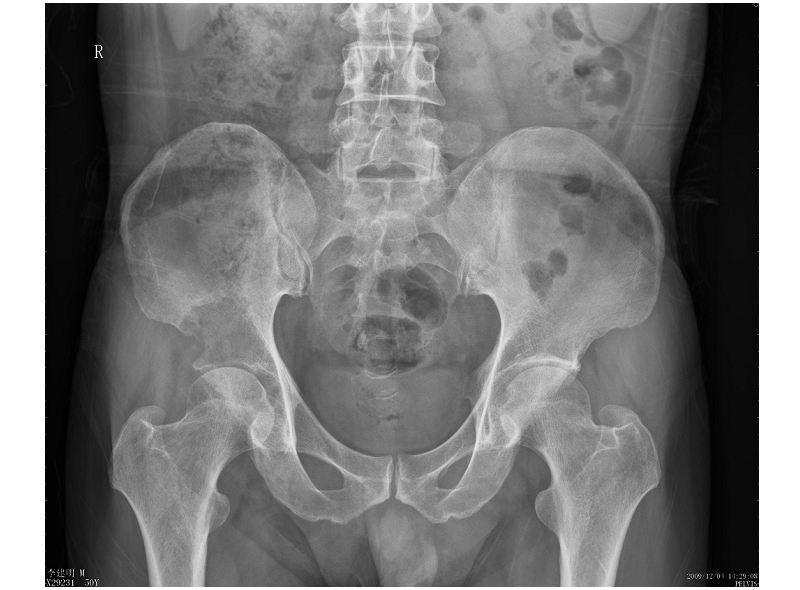

男性,57岁,右髋部疼痛一月

骨质破坏严重,考虑恶性肿瘤。

鉴别:转移>骨恶纤组>骨淋巴瘤>骨纤维肉瘤>恶性骨巨>骨髓瘤>骨原发网状细胞肉瘤。

溶骨性破坏,并软组织肿块,恶性肿瘤,转移瘤可能性大。

右侧髂骨溶骨性骨质破坏,且见有软组织肿块,首选考虑转移瘤,其次考虑淋巴瘤或骨肉瘤。

这个病人肺部纵膈及两侧腋下多发肿大淋巴结,已转院进一步检查。